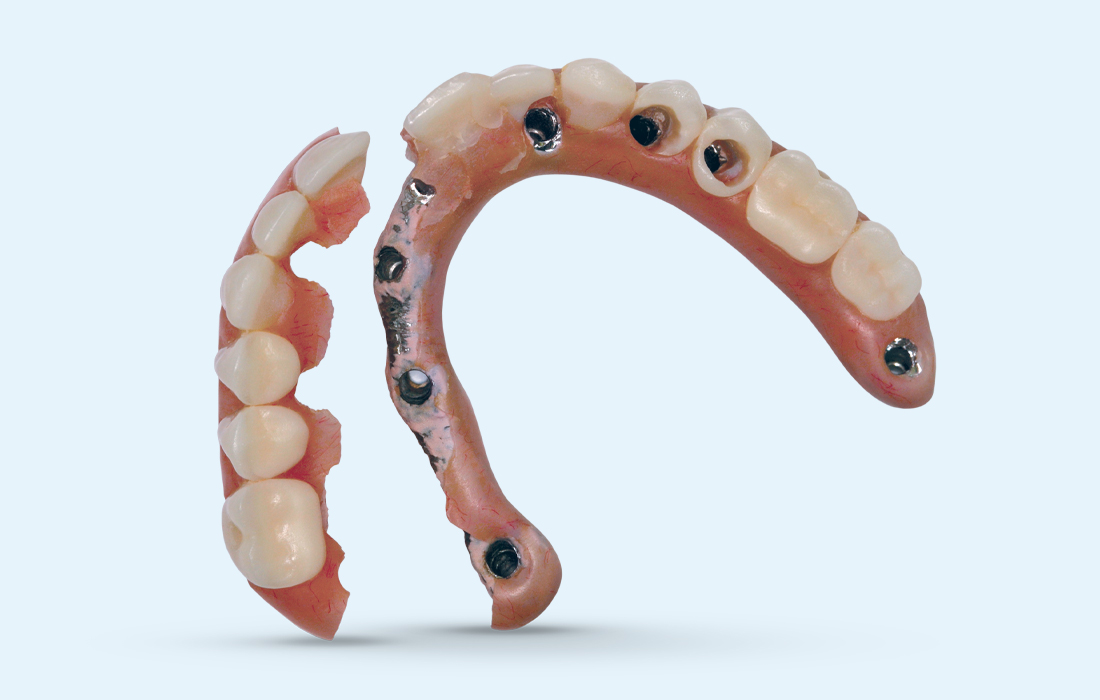

BruxZir Implant Prosthesis Image 1 CSM V15I2

Patient's smile after BruxZir Implant Prosthesis

Dr. Hahn delivered numerous screw-retained hybrid dentures for his edentulous patients prior to the advent of the monolithic zirconia full-arch implant restoration. Now, when patients return to his office with a broken hybrid denture (left), he simply upgrades them to a BruxZir Implant Prosthesis (right), which avoids the damage that commonly occurs with acrylic appliances.